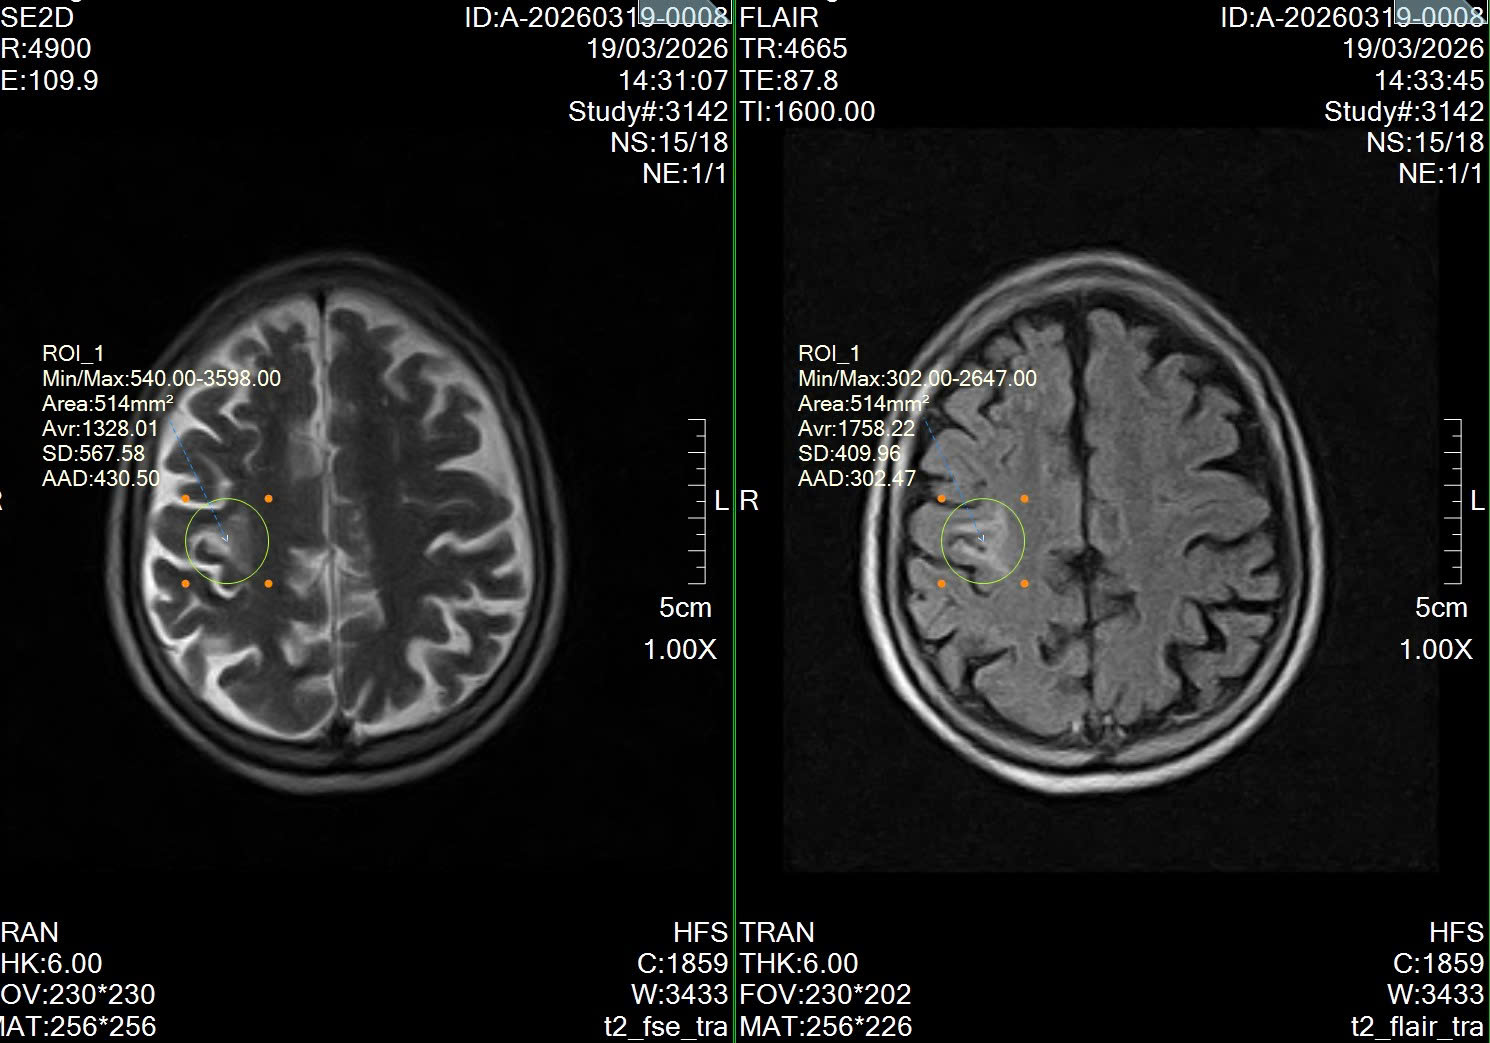

PHÁT HIỆN NHỒI MÁU NÃO QUA CHỤP CỘNG HƯỞNG TỪ MRI SỌ NÃO TẠI PHÒNG KHÁM ĐA KHOA HỒNG HOÀNG

Thứ Fri, 20/03/2026

Hôm qua, tại Phòng khám Đa khoa Hồng Hoàng, các bác sĩ đã phát hiện một trường hợp bệnh nhân bị nhồi máu não thông qua chụp cộng hưởng từ (MRI) sọ não. Bệnh nhân nam, gần 80 tuổi, đến thăm khám v...